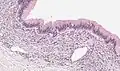

Micrograph showing a mucinous cystadenoma of the ovary. H&E stain.

Mucinous cystadenoma is a benign cystic tumor lined by a mucinous epithelium. It is a type of cystic adenoma (cystadenoma).